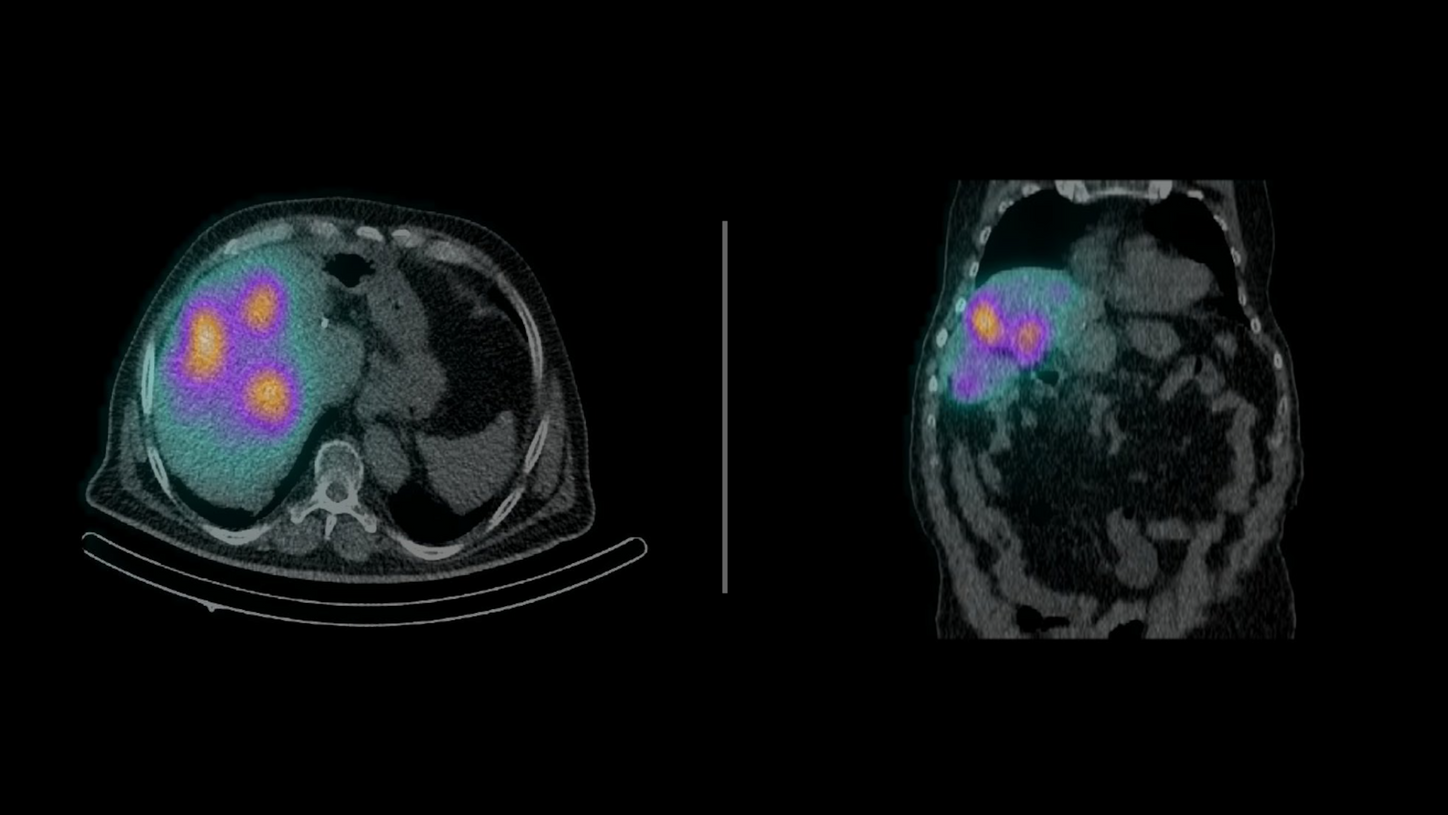

Transitioning to SPECT/CT accelerated the center鈥檚 evolution into a full-fledged theranostics hub. Today, nearly 50 percent of the department鈥檚 cancer patients are treated within theranostics pathways, including radioiodine therapy for thyroid cancer, lutetium-177 for prostate cancer (PSMA therapy) and neuroendocrine tumors (peptide receptor radionuclide therapy), and radioembolization.听

鈥淭he combination of SPECT/CT and personalized dosimetry is critical to providing optimal outcomes in theranostics,鈥 says Koutsikos. 鈥淨uantitative imaging, low-dose diagnostic CT, and improved tumor localization are essential for both patient safety and therapeutic success.鈥澨

Throughout the theranostics process, patients often undergo multiple scans鈥攂efore and after treatment cycles鈥攖o monitor therapeutic uptake and assess effectiveness. This valuable imaging during treatment is one of the great advantages of theranostics, offering clinicians real-time insight into how well a treatment is working. However, it also raises concern about cumulative radiation exposure, particularly for patients undergoing long-term therapies.

Considering these concerns, a critical component of theranostics is dosimetry, the measurement of the absorbed radiation dose in tissues, which helps optimize treatment planning and ensure patient safety. While the dosimetry of radionuclide therapy is important to protect sensitive organs, another measure to reduce exposure is utilization of low-dose CT in subsequent scanning protocols.

Recognizing the importance of minimizing radiation exposure without compromising diagnostic quality, Koutsikos and his team have undertaken a study to evaluate the impact of low-dose CT protocols in their clinical practice. He and his colleagues presented data at the Panhellenic Conference and Balkan Congress of Nuclear Medicine in May 2025 highlighting the reduction in radiation exposure achieved with Symbia Pro.specta鈥檚 low-dose CT protocols, with dose indices reduced by up to a factor of nine compared to European and national reference levels.1听

鈥淲ith theranostic patients undergoing multiple scans throughout treatment, minimizing radiation exposure without compromising image quality is a major advantage,鈥 he adds.